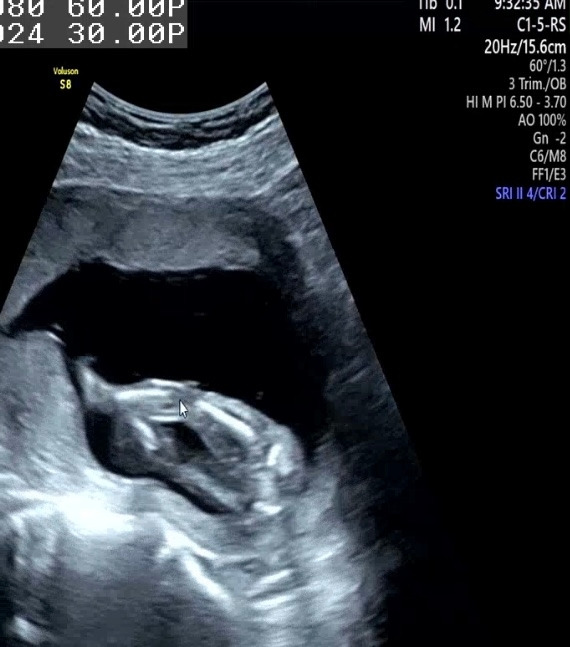

의사 선생님 왈 "공주님 이네요~"